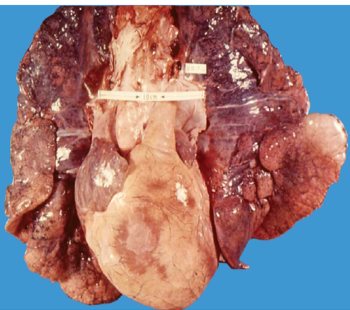

2.心脏病变 心脏体积增大,重量增加,右心室肥厚,心腔扩张,心尖钝圆,主要由右心室构成。肺动脉圆锥显著膨隆,肥厚的右心室内乳头肌、肉柱增粗,室上嵴增厚。通常以肺动脉瓣下2cm处右心室肌壁厚≥5mm(正常约为3~4mm)为肺心病的病理诊断标准。镜下,可见缺氧所致的心肌纤维萎缩,肌浆溶解,横纹消失。尚可见到心肌纤维横径增宽、核大、深染,心肌间质水肿及胶原纤维增生等改变。